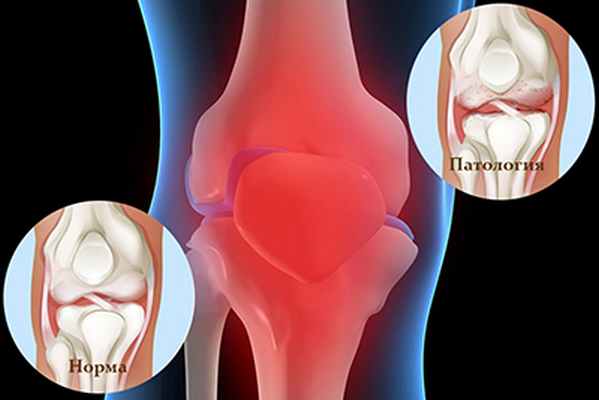

Менископатия — это целая группа патологий, которые характеризуются дегенеративными поражениями мениска. Как правило, заболевание развивается при физическом повреждении и подразумевает нарушение функционирования коленного сустава.

Дегенеративное изменение мениска — это повреждение органа, которое появилось в результате заболеваний, травм или нетипичного строения сустава. Нарушения могут быть различными — отрыв мениска, разрывы его тела или рожек, аномальная подвижность из-за нарушения целостности межменисковых связок, киста, менископатия.

Менископатия — это дистрофические изменения, которые развиваются в результате даже несущественных травм, а также могут быть осложнением ряда заболеваний.

Существует большое количество дегенеративных изменений менисков, самыми распространенными являются:

- истончение (истирание) свободного края мениска;

- центральная дегенерация — уплотнение в центральной области;

- горизонтальные разрывы в центральной части;

- лоскутный разрыв — мелкие разрывы, напоминающие бахрому;

- лоскутный разрыв, связанный с процессом дегенерации;

- фибрилляции мениска;

- разрыв тела мениска или его рожек;

- отрыв мениска от места крепления;

- подвижность мениска по причине разрыва связок;

- кисты внутри хряща;

- изменения, которые провоцируются заболеваниями.

Чаще всего вышеперечисленные изменения сочетаются с повреждением хрящевой ткани. Это может быть как незначительное размягчение, так и существенное оголение субхондрального участка кости.

Мениски - это особые прослойки, располагающиеся внутри коленного сустава и состоящие из фиброволокнистого хряща полулунной формы. Мениски сглаживают несоответствие круглых мыщелков бедренной кости и плоской большеберцовой кости, выполняют амортизирующую и стабилизирующую функции.

Всего в коленном суставе два мениска: внутренний (медиальный) и наружный (латеральный).